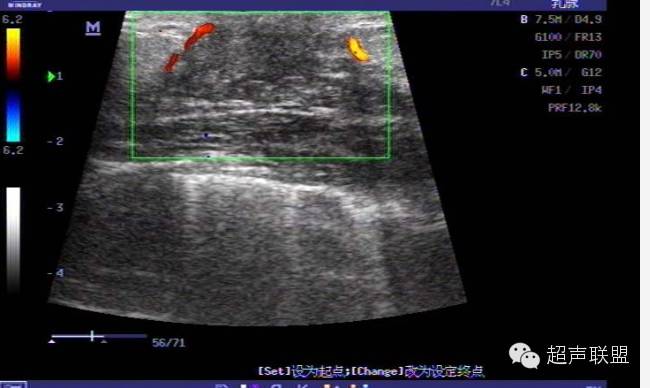

挤压成像对诊断固态肿块十分重要,因为癌变区域的压缩形变较良性肿瘤小得多。有时固态肿块的声学特性相对于周围组织(尤其是脂肪)来说是一致的,因而只能*观测某块区域相对的挤压形变量来检测病变。

弹力图是通过在组织上施加一个微小的压力,比较挤压前后的两幅图像而获得组织的弹性特征。运用互相关法处理挤压前后获得的数据可测定各个小块组织相应于探头压力所产生的位移量。这些挤压幅度很小,通常在0.2到0.6mm之间。乳腺组织位移变化率相对于施压探头距离的变化关系,即为应变图像,进而构成了最后的弹力图。